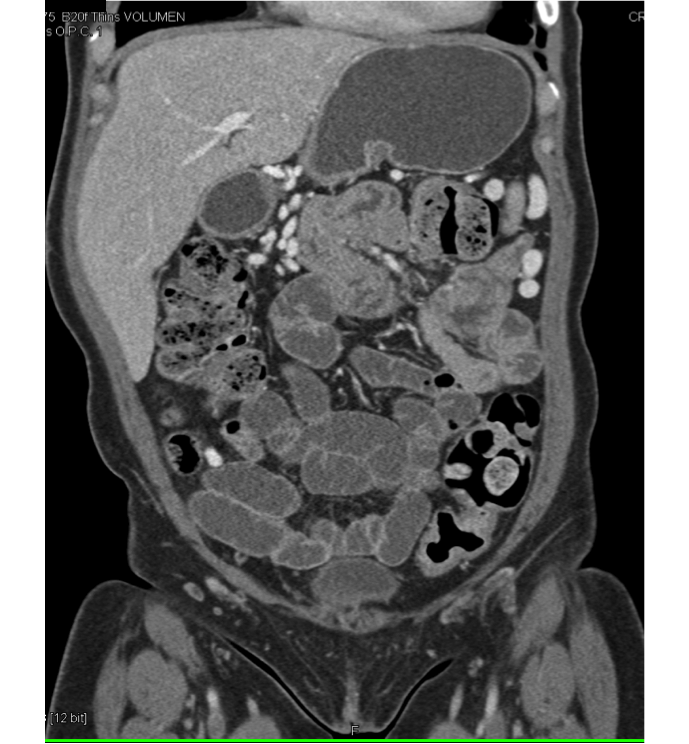

Ct Scan With Contrast Abdomen And Pelvis at Selma Garcia blog What Is The Purpose Of Contrast In A Ct Scan Oral contrast is contrast you take by mouth. Almost always, cts should be ordered with or without contrast, not both. Here is an overview of the indications for contrasted ct: It doesn’t change any of these things, but it. They help your doctor see the organs, blood vessels, and bones in your abdomen. It uses a series of x. Contrast. What Is The Purpose Of Contrast In A Ct Scan.

a Native abdominal CT scan with oral contrast dye at the day of What Is The Purpose Of Contrast In A Ct Scan A ct (computed tomography) scan is an imaging test that helps healthcare providers detect diseases and injuries. Contrast distinguishes, or “ contrasts,” between organs, tissues, bones, or blood vessels during your imaging exam. There are 2 different ways to get contrast: They help your doctor see the organs, blood vessels, and bones in your abdomen. It doesn’t change any of. What Is The Purpose Of Contrast In A Ct Scan.